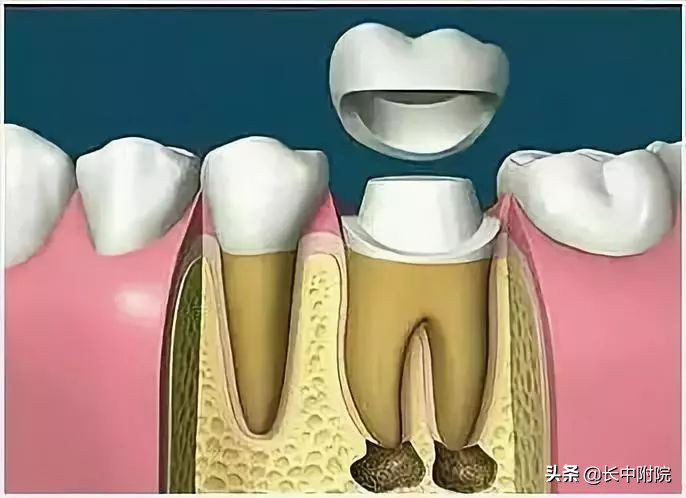

7.根管打桩

因牙体缺损过多,导致牙的强度(承受力量的性能)大幅度下降,不能很好地承受咀嚼力量。打桩的目的是增加牙根及牙冠的强度,增加患牙的稳固。

8.完成牙体修复

X线片显示根管充填完好,行暂时或永久牙体修复,带上牙冠,保护患牙。至此根管治疗才可算完成,同时根管治疗后还需复诊,一般周期可为3个月、半年、1年、2年或更长。